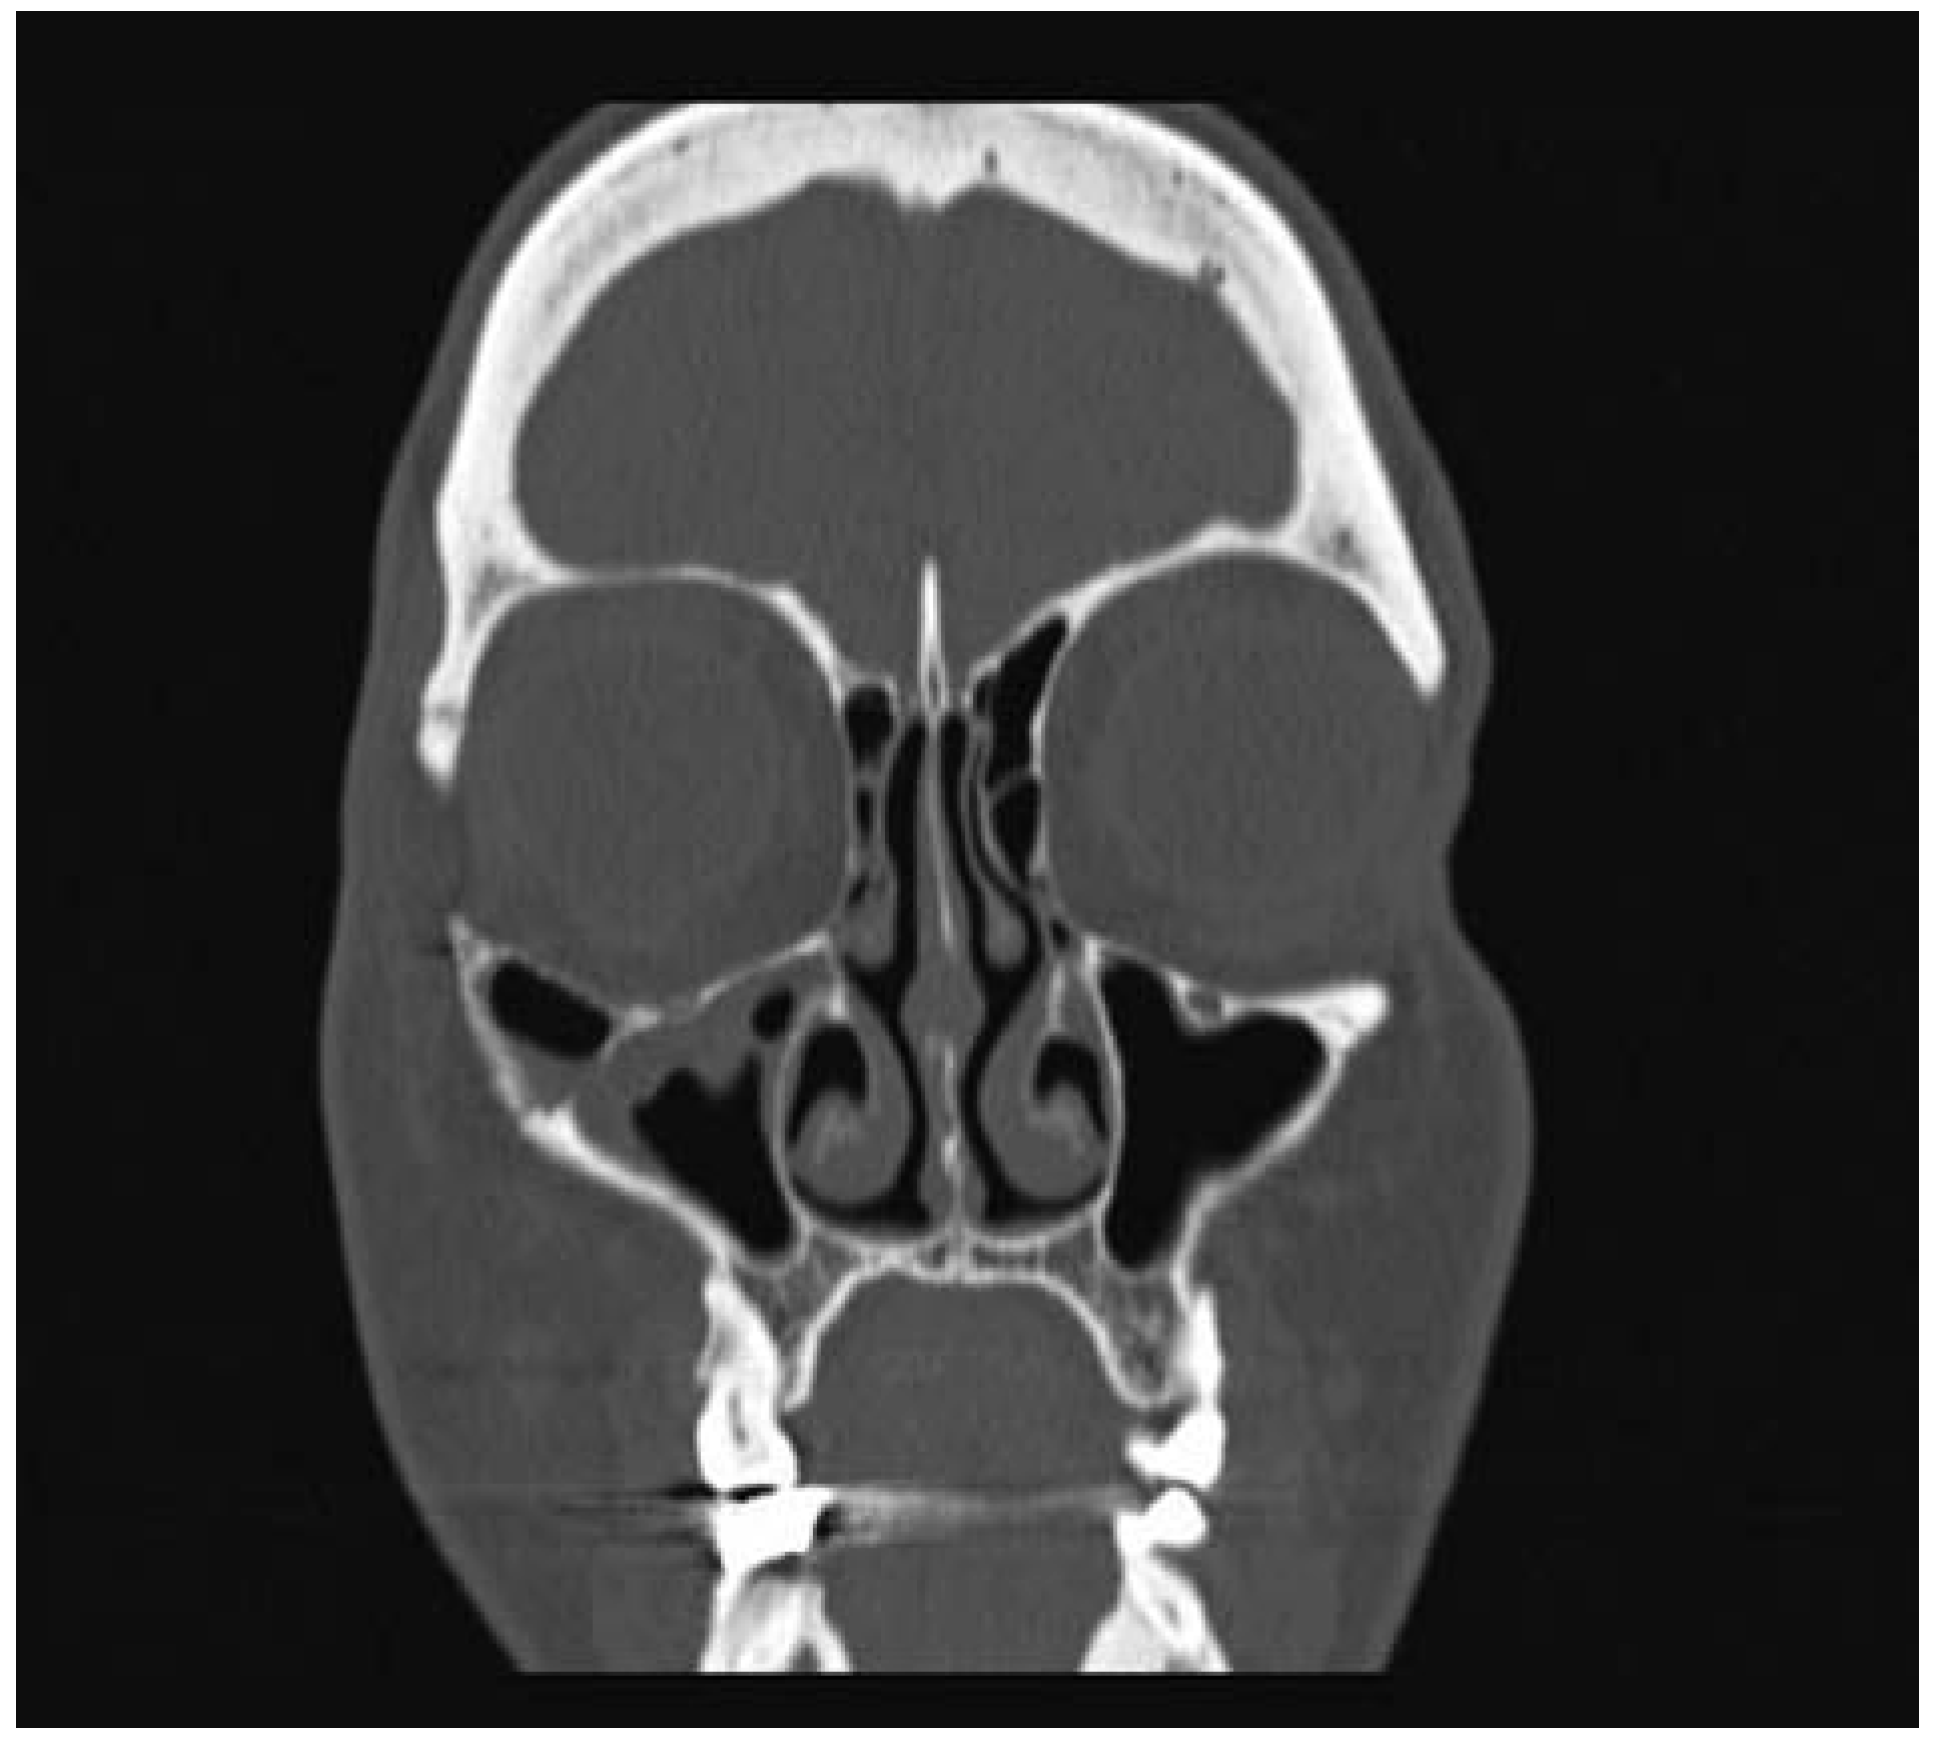

:Case Presentation

- Moore, S.L.; Chun, J.K.; Mitre, S.A.; Som, P.M. Intraosseous hemangioma of the zygoma: CT and MR findings. AJNR Am J Neuroradiol 2001, 22, 1383–1385. [Google Scholar] [PubMed]

- Razek, A.A. Imaging appearance of bone tumors of the maxillofacial region. World J Radiol 2011, 3, 125–134. [Google Scholar] [PubMed]

- Gonçalves, F.G.; Rojas, J.P.; Hanagandi, P.B.; et al. Case report: Periorbital intraosseous hemangiomas. Indian J Radiol Imaging 2011, 21, 287–290. [Google Scholar]